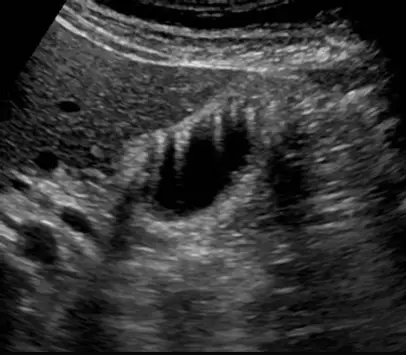

下圖膽囊超音波檢查,在膽囊呈現多條線狀高回音,為下列何種假影(artifact )?

本題提供了一張膽囊(gallbladder)的超音波掃描影像。在影像中,可以清楚觀察到膽囊壁有局部增厚的現象,並且從增厚的膽囊壁向著無回音(anechoic)的膽囊腔內部,延伸出多條呈現倒三角形、明亮的線狀高回音(hyperechoic linear echoes)。這些高回音訊號呈現上寬下窄的漸弱形狀,且訊號條紋間距極短,這是非常典型的「彗星尾假影」(comet tail artifact)。在臨床膽囊超音波掃描中,這種影像特徵常見於膽囊腺肌瘤症(adenomyomatosis),其主要成因為膽囊壁內擴張的 Rokitansky-Aschoff sinuses 中沉積了微小且具高反射性的膽固醇結晶(cholesterol crystals)所引起。

- (A) comet tail (reverberation) artifact:正確。彗星尾假影屬於迴響假影(reverberation artifact)的一種特殊形式。當超音波波束遇到極微小且相距極近的強反射介面(如膽固醇結晶)時,聲波會在這些介面之間發生多次來回反射。超音波儀器將這些延遲接收到的回音誤判為來自更深處的組織,從而在真實反射物體後方,產生一連串間距極窄、因能量衰減而呈現倒三角形的連續高回音線條,完全符合題目影像與題幹「多條線狀高回音」的描述。

綜合上述影像特徵與超音波物理機制,影像中從膽囊壁向腔內放射的「多條線狀高回音」確切符合 comet tail artifact 的定義。在膽囊超音波檢查中,這種特徵是聲波在膽固醇結晶內部發生微小迴響(reverberation)的結果。由於其他選項的物理機制與影像表現皆與本題圖片完全不同,因此 (A) 為唯一正確且最佳的答案。